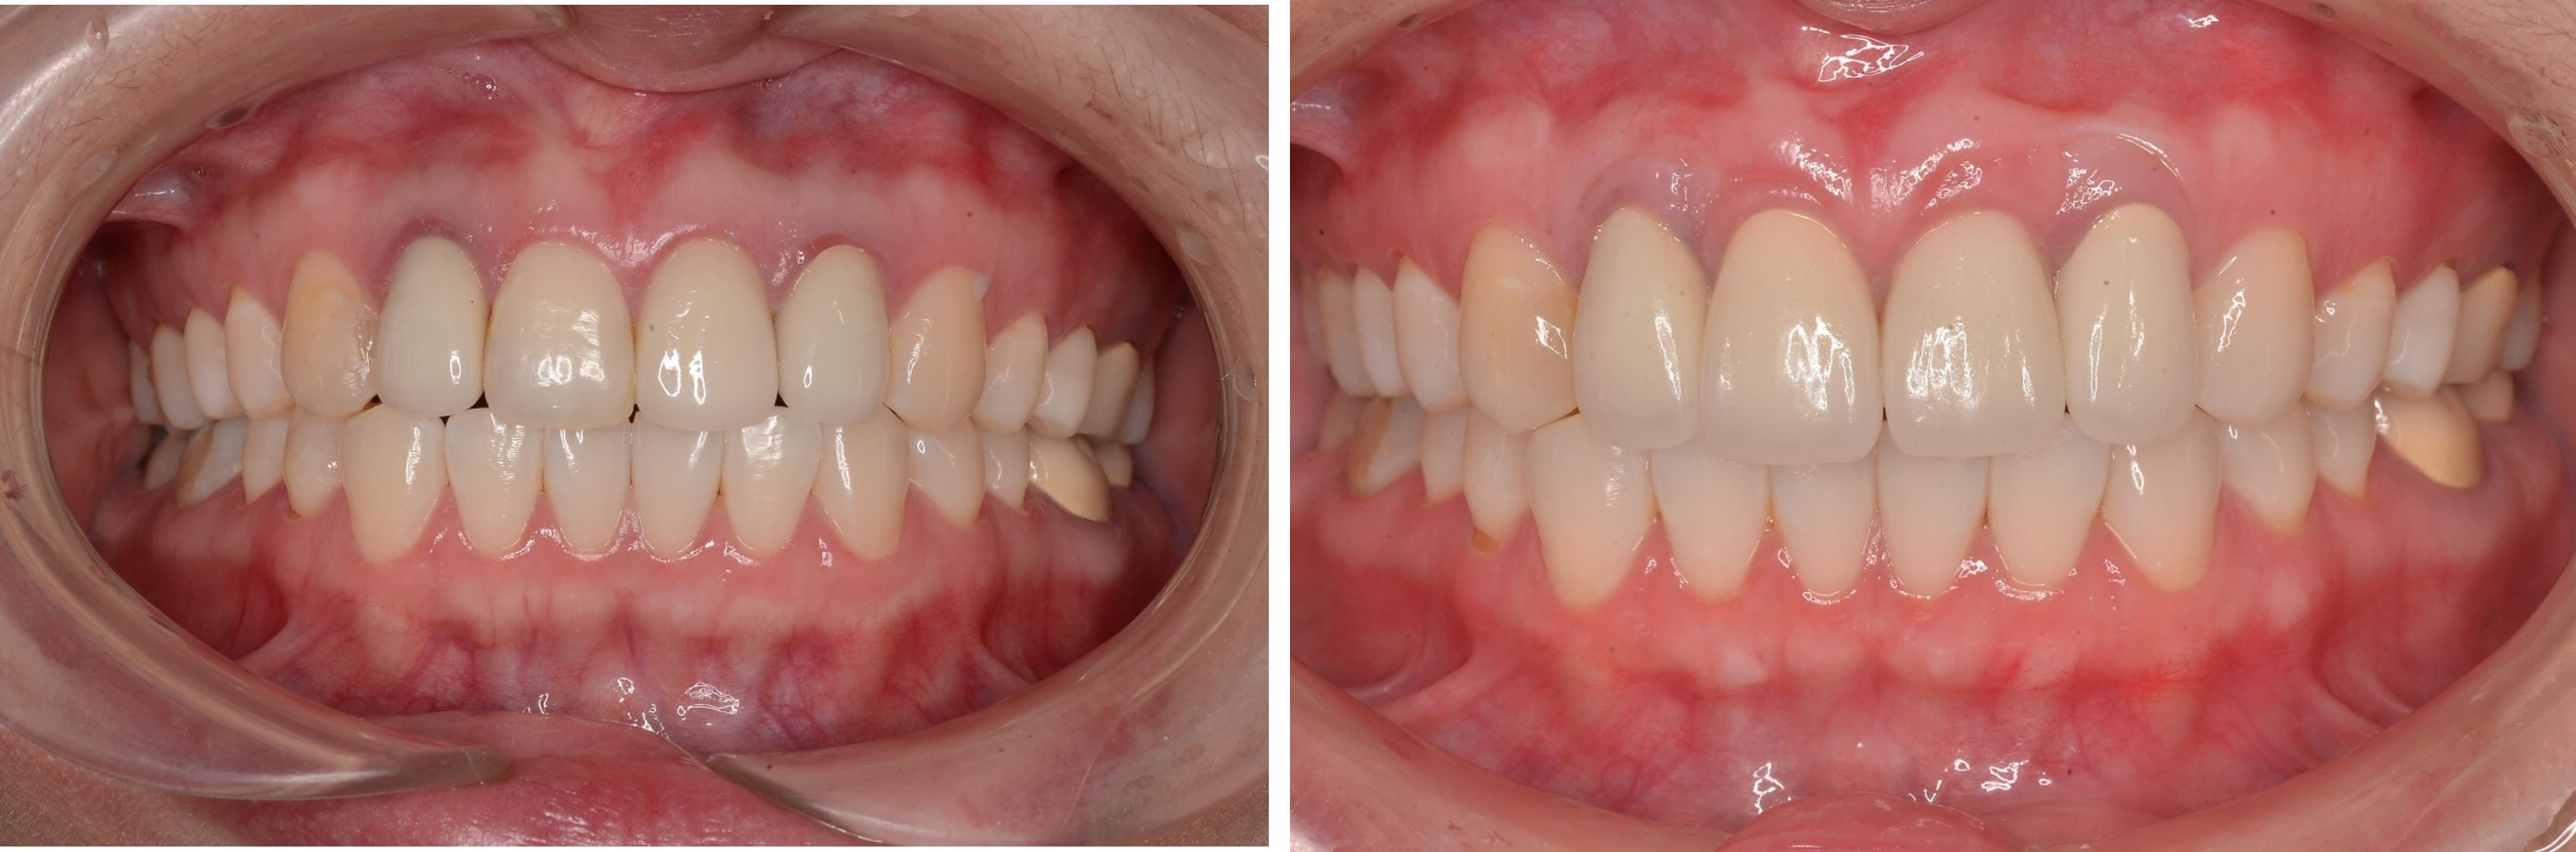

前牙美學與口腔重建-牙齒變色及根尖病變-#全口

口腔重建

前牙美學